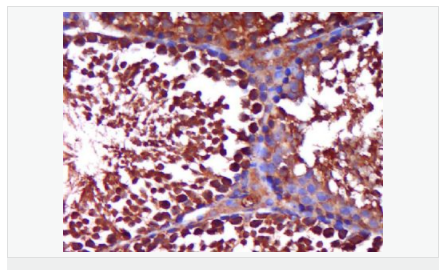

| 產品介紹 | The androgen receptor gene is more than 90 kb long and codes for a protein that has 3 major functional domains: the N-terminal domain, DNA-binding domain, and androgen-binding domain. The protein functions as a steroid-hormone activated transcription factor. Upon binding the hormone ligand, the receptor dissociates from accessory proteins, translocates into the nucleus, dimerizes, and then stimulates transcription of androgen responsive genes. This gene contains 2 polymorphic trinucleotide repeat segments that encode polyglutamine and polyglycine tracts in the N-terminal transactivation domain of its protein. Expansion of the polyglutamine tract causes spinal bulbar muscular atrophy (Kennedy disease). Mutations in this gene are also associated with complete androgen insensitivity (CAIS). Two alternatively spliced variants encoding distinct isoforms have been described. [provided by RefSeq, Jul 2008] Function: Steroid hormone receptors are ligand-activated transcription factors that regulate eukaryotic gene expression and affect cellular proliferation and differentiation in target tissues. Transcription factor activity is modulated by bound coactivator and corepressor proteins. Transcription activation is down-regulated by NR0B2. Activated, but not phosphorylated, by HIPK3 and ZIPK/DAPK3. [ENZYME REGULATION] AIM-100 (4-amino-5,6-biaryl-furo[2,3-d]pyrimidine) suppresses TNK2-mediated phosphorylation at Tyr-267. Inhibits the binding of the Tyr-267 phosphorylated form to androgen-responsive enhancers (AREs) and its transcriptional activity. Subunit: Binds DNA as a homodimer. Part of a ternary complex containing AR, EFCAB6/DJBP and PARK7. Interacts with HIPK3 and NR0B2 in the presence of androgen. The ligand binding domain interacts with KAT7/HBO1 in the presence of dihydrotestosterone. Interacts with EFCAB6/DJBP, PELP1, PQBP1, RANBP9, RBAK, SPDEF, SRA1, TGFB1I1, ZNF318 and RREB1. Interacts with ZMIZ1/ZIMP10 and ZMIZ2/ZMIP7 which both enhance its transactivation activity. Interacts with SLC30A9 and RAD54L2/ARIP4. Interacts via the ligand-binding domain with LXXLL and FXXLF motifs from NCOA1, NCOA2, NCOA3, NCOA4 and MAGEA11. The AR N-terminal poly-Gln region binds Ran resulting in enhancement of AR-mediated transactivation. Ran-binding decreases as the poly-Gln length increases. Interacts with HIP1 (via coiled coil domain). Interacts (via ligand-binding domain) with TRIM68. Interacts with TNK2. Interacts with USP26. Interacts with RNF6. Interacts (regulated by RNF6 probably through polyubiquitination) with RNF14; regulates AR transcriptional activity. Interacts with PRMT2 and TRIM24. Interacts with GNB2L1/RACK1. Interacts with RANBP10; this interaction enhances dihydrotestosterone-induced AR transcriptional activity. Interacts with PRPF6 in a hormone-independent way; this interaction enhances dihydrotestosterone-induced AR transcriptional activity. Interacts with STK4/MST1. Interacts with ZIPK/DAPK3. Interacts with LPXN. Interacts with MAK. Part of a complex containing AR, MAK and NCOA3. Subcellular Location: Nucleus. Cytoplasm. Note=Predominantly cytoplasmic in unligated form but translocates to the nucleus upon ligand-binding. Can also translocate to the nucleus in unligated form in the presence of GNB2L1. Tissue Specificity: Isoform 2 is mainly expressed in heart and skeletal muscle. Post-translational modifications: Sumoylated on Lys-386 (major) and Lys-520. Ubiquitinated. Deubiquitinated by USP26. 'Lys-6' and 'Lys-27'-linked polyubiquitination by RNF6 modulates AR transcriptional activity and specificity. Phosphorylated in prostate cancer cells in response to several growth factors including EGF. Phosphorylation is induced by c-Src kinase (CSK). Tyr-534 is one of the major phosphorylation sites and an increase in phosphorylation and Src kinase activity is associated with prostate cancer progression. Phosphorylation by TNK2 enhances the DNA-binding and transcriptional activity and may be responsible for androgen-independent progression of prostate cancer. Phosphorylation at Ser-81 by CDK9 regulates AR promoter selectivity and cell growth. Phosphorylation by PAK6 leads to AR-mediated transcription inhibition. Palmitoylated by ZDHHC7 and ZDHHC21. Palmitoylation is required for plasma membrane targeting and for rapid intracellular signaling via ERK and AKT kinases and cAMP generation. DISEASE: Defects in AR are the cause of androgen insensitivity syndrome (AIS) [MIM:300068]; previously known as testicular feminization syndrome (TFM). AIS is an X-linked recessive form of pseudohermaphroditism due end-organ resistance to androgen. Affected males have female external genitalia, female breast development, blind vagina, absent uterus and female adnexa, and abdominal or inguinal testes, despite a normal 46,XY karyotype. Defects in AR are the cause of spinal and bulbar muscular atrophy X-linked type 1 (SMAX1) [MIM:313200]; also known as Kennedy disease. SMAX1 is an X-linked recessive form of spinal muscular atrophy. Spinal muscular atrophy refers to a group of neuromuscular disorders characterized by degeneration of the anterior horn cells of the spinal cord, leading to symmetrical muscle weakness and atrophy. SMAX1 occurs only in men. Age at onset is usually in the third to fifth decade of life, but earlier involvement has been reported. It is characterized by slowly progressive limb and bulbar muscle weakness with fasciculations, muscle atrophy, and gynecomastia. The disorder is clinically similar to classic forms of autosomal spinal muscular atrophy. Note=Caused by trinucleotide CAG repeat expansion. In SMAX1 patients the number of Gln ranges from 38 to 62. Longer expansions result in earlier onset and more severe clinical manifestations of the disease. Note=Defects in AR may play a role in metastatic prostate cancer. The mutated receptor stimulates prostate growth and metastases development despite of androgen ablation. This treatment can reduce primary and metastatic lesions probably by inducing apoptosis of tumor cells when they express the wild-type receptor. Defects in AR are the cause of androgen insensitivity syndrome partial (PAIS) [MIM:312300]; also known as Reifenstein syndrome. PAIS is characterized by hypospadias, hypogonadism, gynecomastia, genital ambiguity, normal XY karyotype, and a pedigree pattern consistent with X-linked recessive inheritance. Some patients present azoospermia or severe oligospermia without other clinical manifestations. Similarity: Belongs to the nuclear hormone receptor family. NR3 subfamily. Contains 1 nuclear receptor DNA-binding domain. SWISS: P10275 Gene ID: 367 Database links: Entrez Gene: 367 Human Entrez Gene: 11835 Mouse Omim: 313700 Human SwissProt: P10275 Human SwissProt: P19091 Mouse Unigene: 496240 Human Unigene: 39005 Mouse Unigene: 394224 Mouse Unigene: 439657 Mouse Unigene: 9813 Rat Important Note: This product as supplied is intended for research use only, not for use in human, therapeutic or diagnostic applications. AR是一個由917個氨基酸組成的蛋白質,位于雄激素靶組織細胞中或細胞表面上的特異分子部位或結構。 AR在前列腺癌中起著重要的作用,研究表明AR的表達與組織分型形成一定的相關性 ,AR在高分化的腫瘤中表達較多,而在低分化的腫瘤中表達較少。用于前列腺癌的檢測,指導臨床治療,目前可用于乳腺癌、食道癌等各項腫瘤的研究。 |